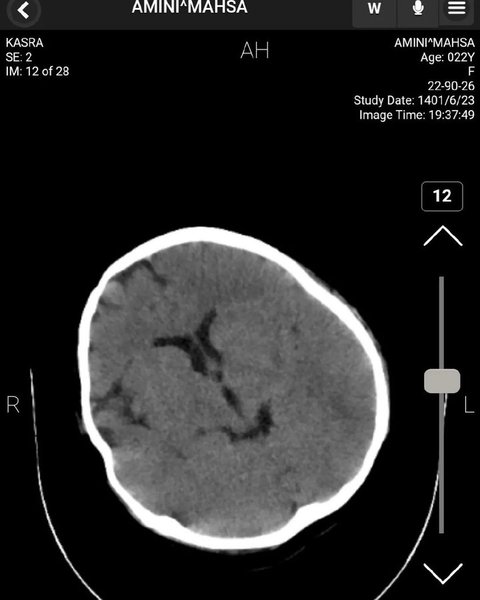

У Twitter якогось Мохаммада, який представився нейрохірургом, опубліковано знімки томографії головного мозку Махси з коментарями.

Згідно з висновком нейрохірурга, на КТ голови Махси не виявлено жодних ознак травми мозку, черепної коробки та кровотечі. На знімках видно сліди зробленої раніше операції.

мозок, голова, КТ, Махса Аміні

КТ голови Махси Аміні

"Ознаки хірургічного втручання є, вони свідчать про лобово-скроневу краніотомію з короткочасною атрофією м'язів та зміни м'яких тканин", — коментує хірург.

Так, за даними нейрохірурга, смерть Махси не могла статися від травм головного мозку.